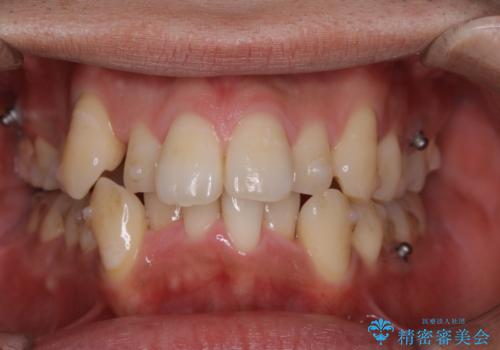

- インビザラインでの矯正治療中に、アタッチメント周囲のステインが気になるとのことでした。PMTC30分コースで、特に見える表側のステイン除去を行いました。

矯正治療中もPMTCを定期的に行い、専門的な機械でしっかりと汚れを除去することがおススメです。

30分コースでは主に前歯をメインに行います。